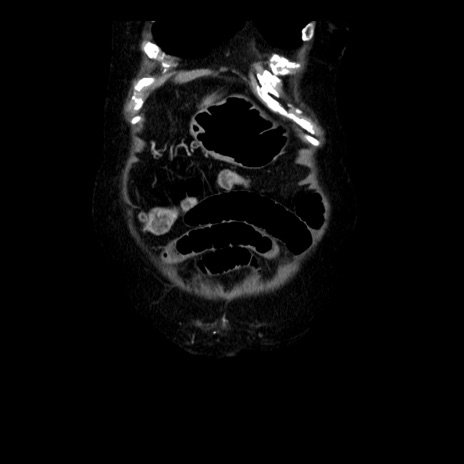

横断像

【症例】 90歳代女性

【主訴】 腹痛・嘔吐

【現病歴】今朝から左側腹部痛を認めた。 経過観察していたが、嘔吐を認めたため来院。

【既往歴】 子宮癌術後

【身体所見】 意識清明、BP 127/54mmHg、P 98bpm Sp02 95%(RA)、BT 35.8°C、腹部平坦・軟腸ぜん動音聴取良好、右下腹部圧痛(+) 反跳痛なし

【データ】WBC 9800、CRP 0.46